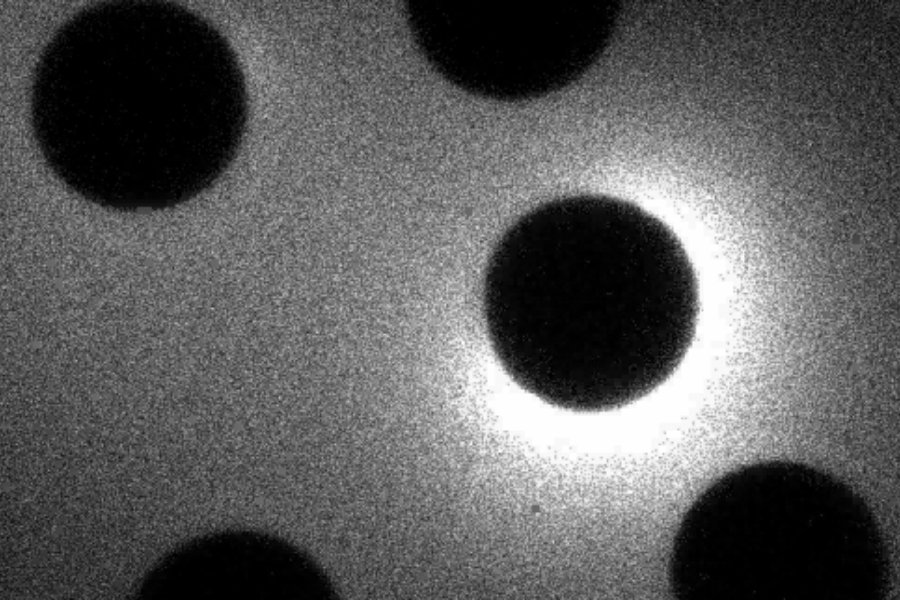

Tia sáng ấy được gọi là tia sáng kẽm (zinc spark). Đây là hiện tượng trứng giải phóng một lượng lớn ion kẽm ngay lúc được kích hoạt trong quá trình thụ tinh. Dấu hiệu này cho thấy trứng đã chuyển sang trạng thái sẵn sàng phát triển thành phôi.

Chính sự tái phân phối kẽm này tạo ra hiện tượng mà các nhà khoa học gọi là tia sáng kẽm. Khi trứng được kích hoạt, các ion kẽm đồng loạt phóng thích ra ngoài trong một thời gian cực ngắn. Những ion này gắn vào các phân tử huỳnh quang đặc biệt, tạo nên tín hiệu phát sáng có thể được nhìn thấy dưới kính hiển vi.

Dù tia sáng không thể nhìn bằng mắt thường, công nghệ hình ảnh chuyên biệt cho thấy nó xuất hiện như một đợt lóe nhẹ bao quanh trứng.

Khám phá về tia sáng kẽm mang đến một hướng tiếp cận mới cho lĩnh vực hỗ trợ sinh sản. Khi trứng được kích hoạt, sự phóng thích kẽm tạo ra tín hiệu huỳnh quang có thể quan sát bằng kính hiển vi chuyên dụng.

Một số nghiên cứu tiền lâm sàng cho thấy cường độ của tia sáng này phản ánh khả năng trứng bước vào quá trình phát triển phôi, từ đó mở ra triển vọng sử dụng tia sáng kẽm như một dấu hiệu sinh học để đánh giá chất lượng trứng ngay lập tức.

Khi ánh sáng rõ và mạnh, trứng có thể thuộc nhóm có tiềm năng phát triển tốt. Ngược lại, ánh sáng yếu hoặc không xuất hiện có thể phản ánh triển vọng thấp hơn. Đây là phương pháp không xâm lấn và có khả năng cung cấp thông tin tức thời về chất lượng trứng.

Lượng kẽm được giải phóng càng lớn thì tia sáng càng rõ. Độ sáng ấy có thể cho chúng ta hình dung về khả năng phát triển của trứng ngay trước khi tiến hành thụ tinh.